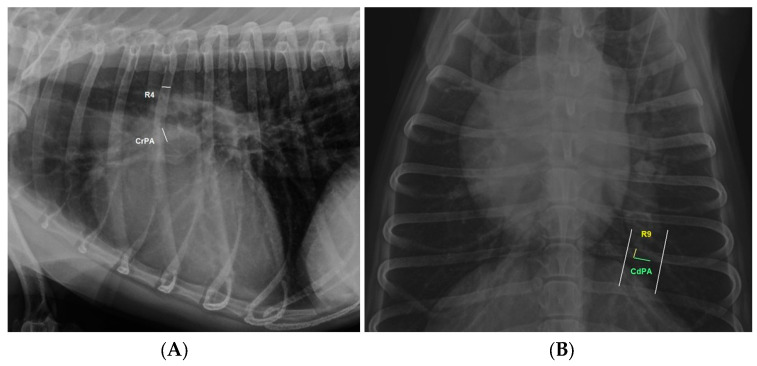

In addition, the diameter of the right cranial pulmonary artery (CrPA) passing through the fourth rib (R4) in the laterolateral projection and the diameter of R4 at a point just distal to the spine, as well as the distal and left sides of the summation shadow created by the right caudal pulmonary artery (CdPA) with the ninth rib (R9) in the dorsoventral projection, were also measured according to previous guidelines [17]. CrPA/R4 and CdPA/R9 ratios were calculated from these measurements (Figure 1). Measurements were performed using electronic callipers on a DICOM workstation (DAIPACS. 2.71 version). All measurements were performed by the same technician, blinded to the clinical status of the dogs included in this study.

Figure 1.

Right laterolateral (A) and dorsoventral (B) thoracic radiographs illustrating the measurement methods for this study. (A) The diameter of the right cranial lobar artery (CrPA) at the level of the fourth rib (R4) and the fourth rib just distal to the spine were measured, and (B) the diameter of the caudal lobar artery (CdPA) passing through the ninth rib (R9).